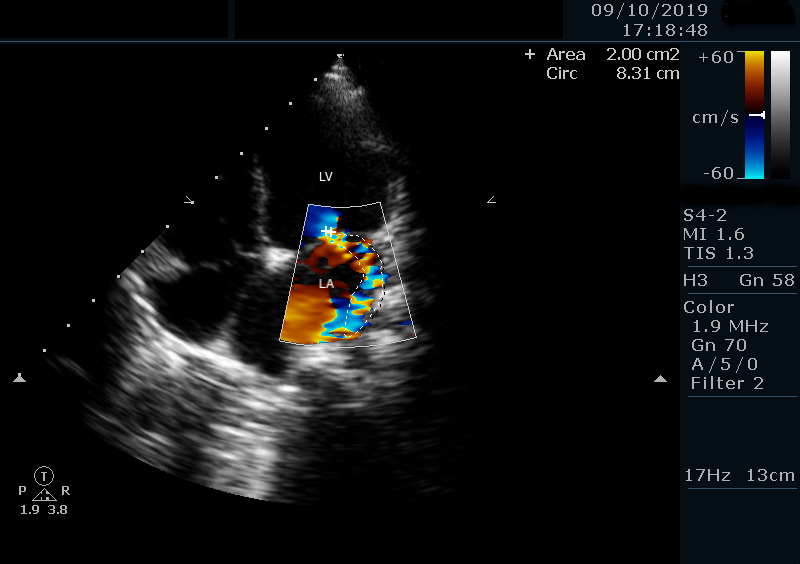

A previously healthy 6-year-old girl from a rural, socioeconomically disadvantaged background presented with a 2-week history of persistent high-grade fever, fatigue, and poor oral intake. She had no prior cardiac or chronic illnesses. Initial management for presumed enteric fever was unsuccessful. On admission, she was febrile (38.5°C), tachycardic (110 bpm), normotensive (90/70 mmHg), and had a grade III/VI pansystolic murmur. The rest of the exam was unremarkable. Labs showed leukocytosis (WBC 17,500/μL) with neutrophilia and elevated inflammatory markers. Chest X-ray and abdominal ultrasound were normal. Transthoracic echocardiography (TTE) revealed a mobile 11 mm vegetation on the anterior mitral leaflet with severe mitral regurgitation (Figure 1). Blood cultures grew methicillin-resistant Staphylococcus aureus (MRSA). IV vancomycin and gentamicin were initiated. No anticoagulation was given. Cranial CT and neurologic assessment were normal. After 14 days, repeat TTE showed a reduction in vegetation size to 8 mm. She remained afebrile and clinically improved. Antibiotics were continued for 6 weeks. A follow-up echo 4 weeks post-discharge showed complete resolution of the vegetation with persistent moderate mitral regurgitation (Figure 2). No embolic or neurologic events occurred. At 3-year follow-up, TTE confirmed no vegetation recurrence and stable MR (Figure 3) .